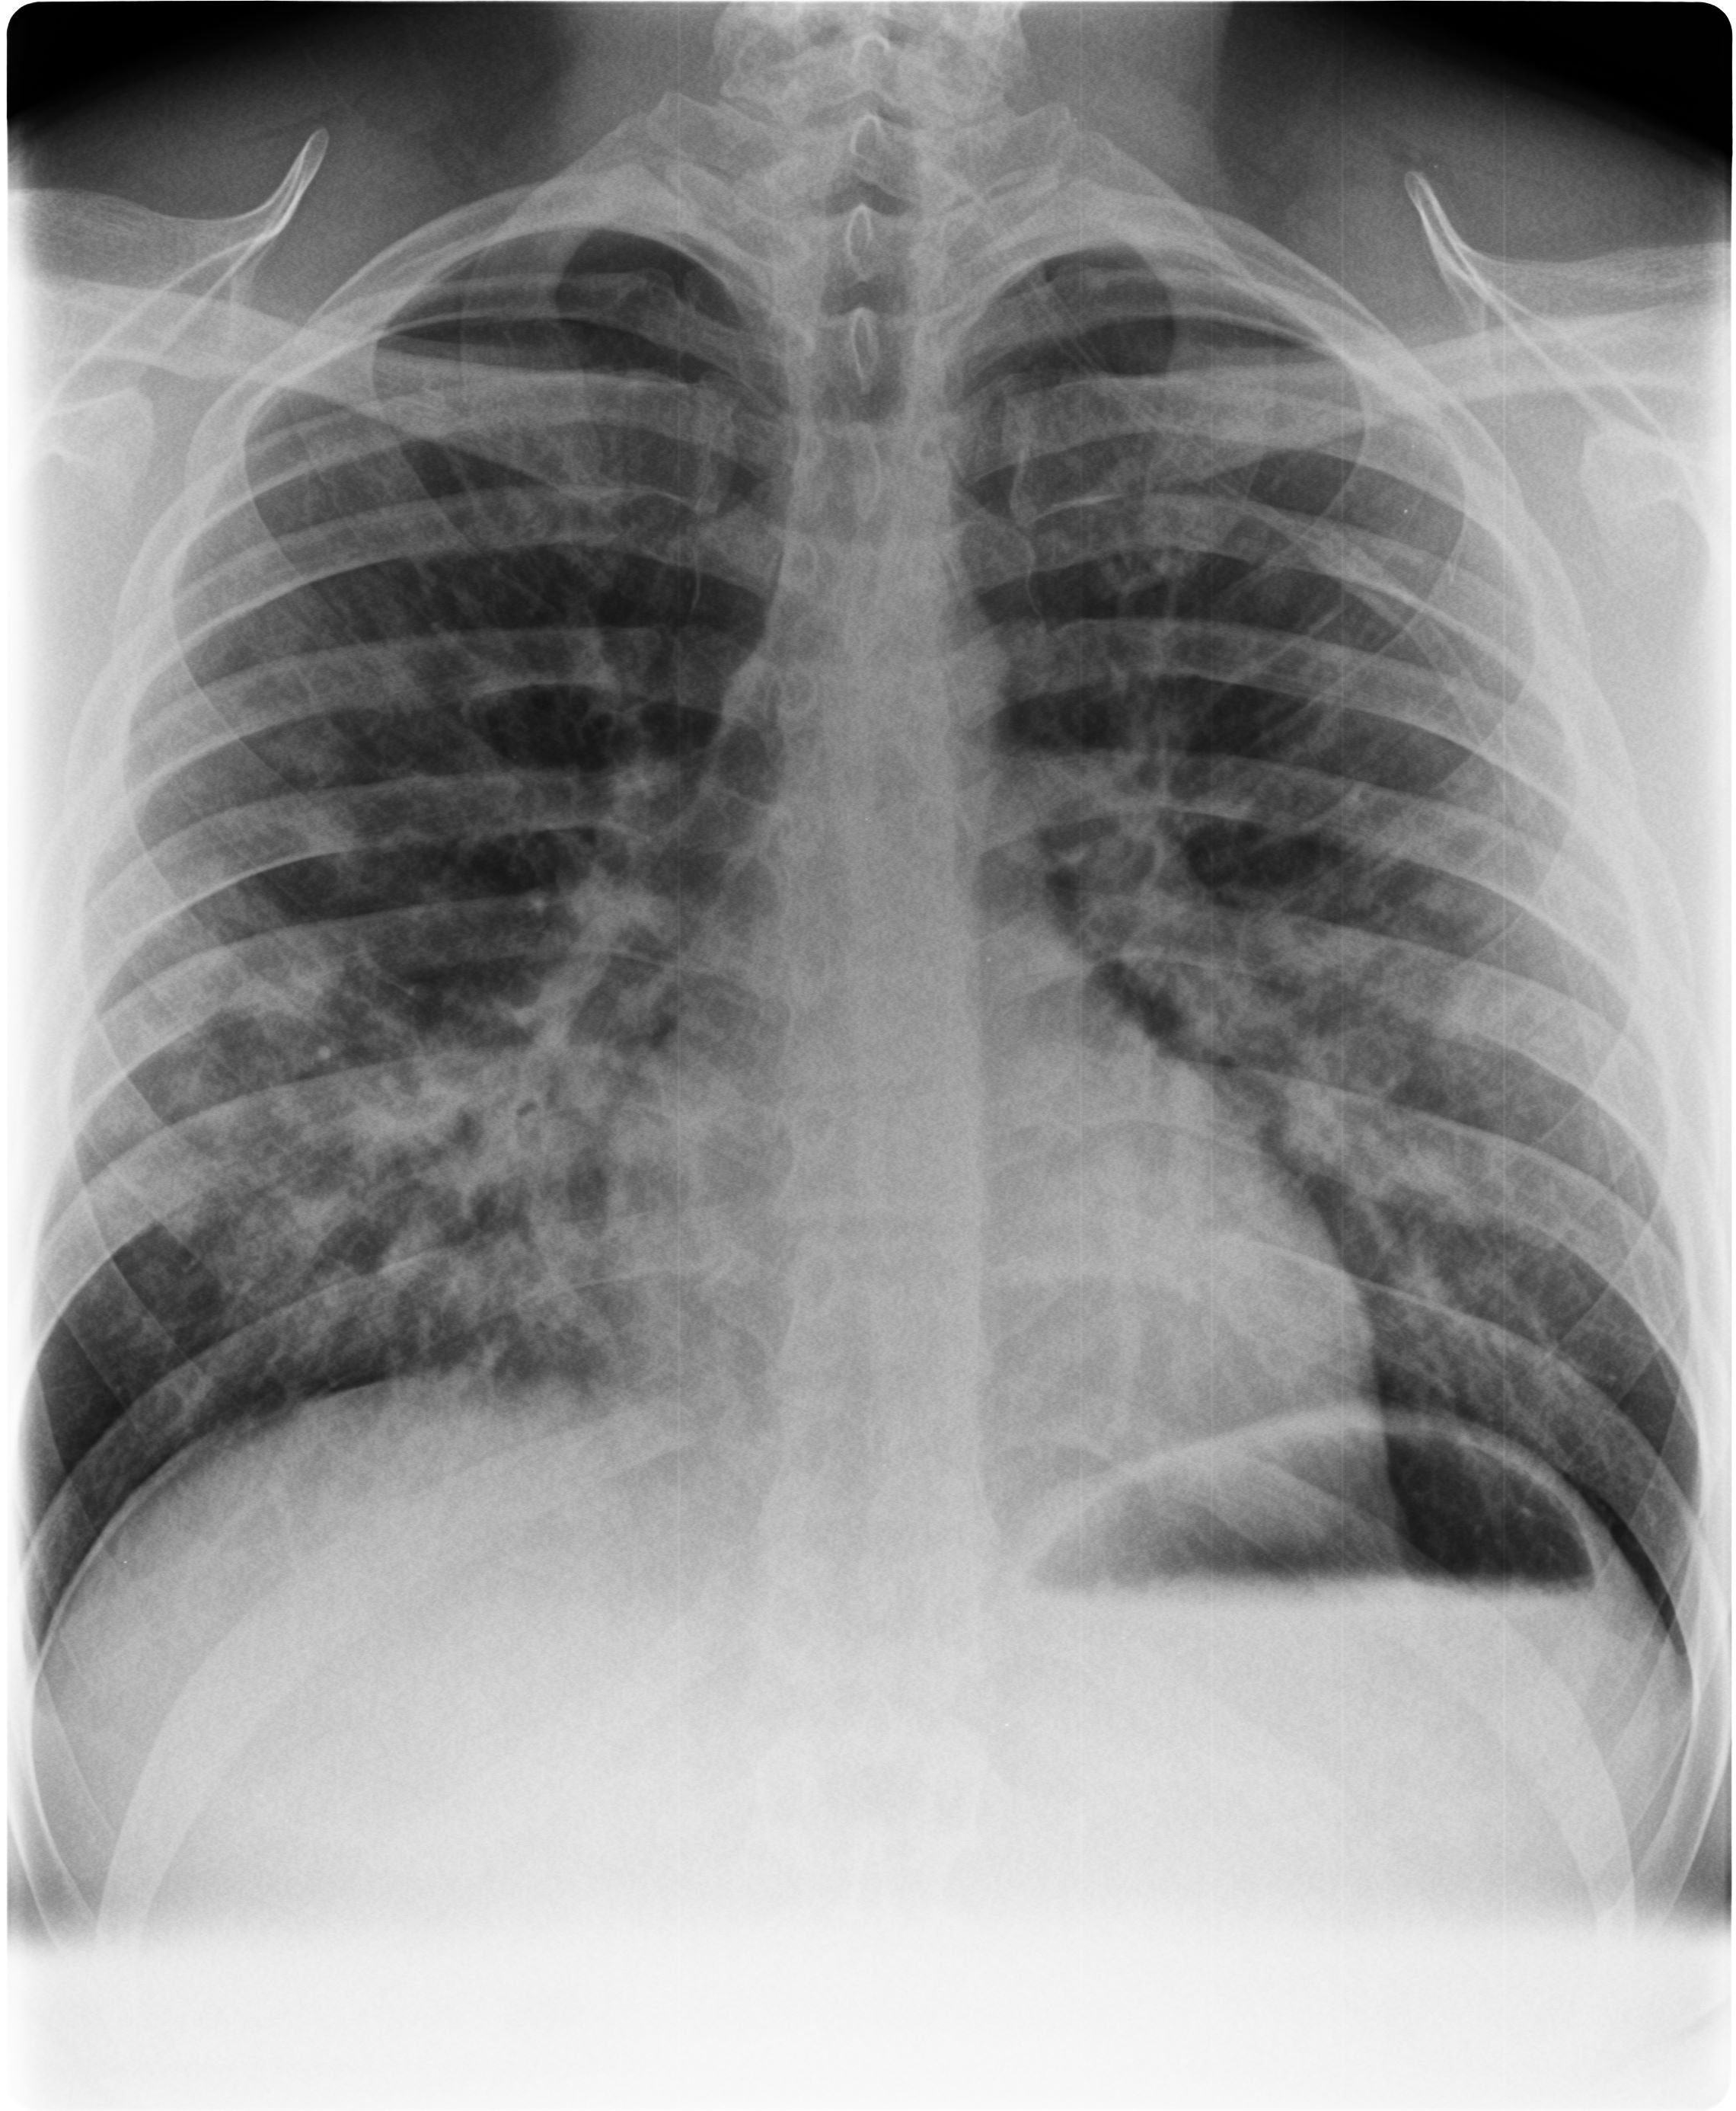

High Altitude Pulmonary Edema: Day 1

Day 1 after of presentation, Patchy interstitial infiltrates in R middle lobe